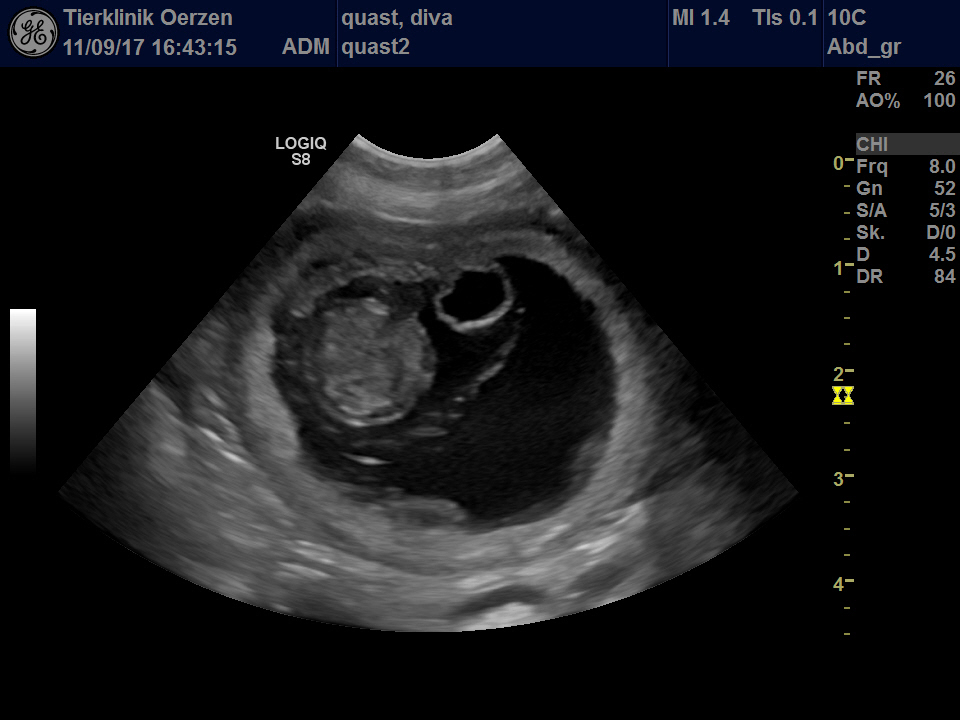

Das erste Foto :-) eindeutig ein dreifarbiger Rüde - ha ha ha